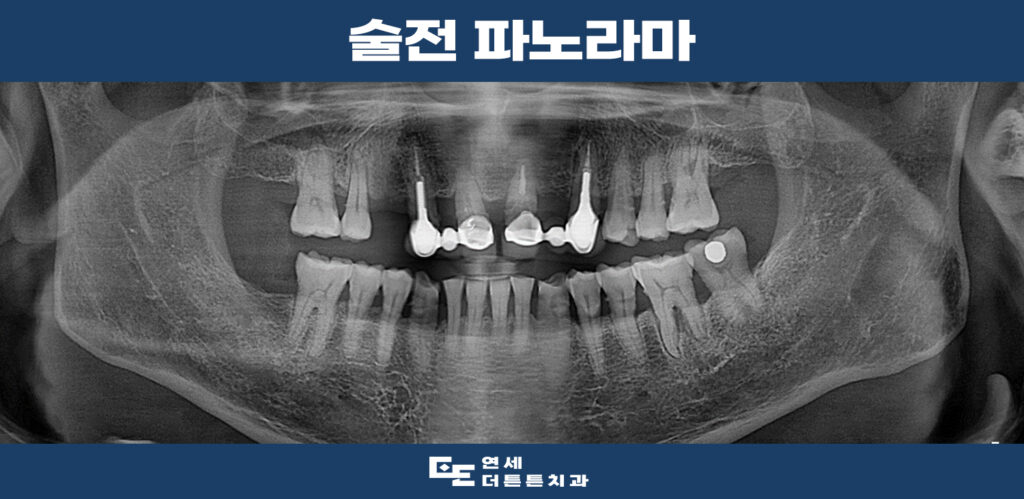

파노라마 촬영 결과, 오른쪽 위아래와

왼쪽 위까지 어금니가 1개씩 상실되었고

오른쪽의 작은 어금니 1개도 상실된

상태였는데요.

더 큰 문제는 씌워두었던 앞니 브릿지가

오래되다 보니 상태가 좋지 않아

살려 쓸 수 있는 것은 살리고 나머지는

임플란트 식립을 진행하시기로 계획을

수립하였습니다.